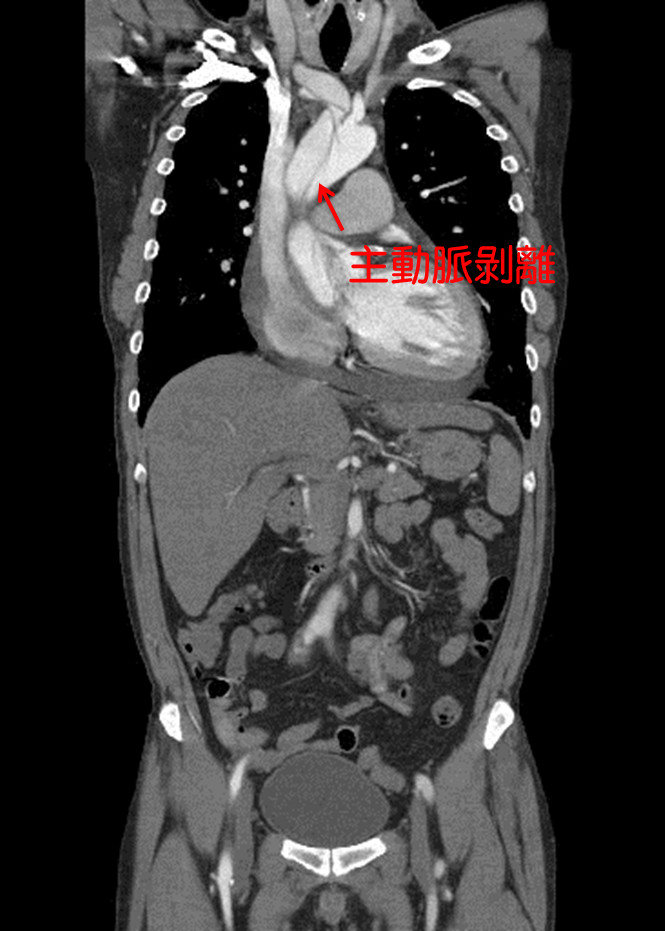

36歲藝人「小鬼」黃鴻升16日趴在家中臥室猝死,震驚全台,解剖後,檢方初判死因是主動脈剝離的心血管問題。急診室醫師說明,主動脈剝離會出現劇烈胸痛,「痛到背後,像被人從後砍一刀」;心臟外科醫師也說,猝死最常見的就是心肌梗塞,「有人連急救時間都沒有」,而主動脈剝離就像剝橘子皮,過程相當兇猛!

檢警18日會同法醫解剖,初步發現有主動脈剝離的狀況,疑似是心血管問題致死,詳細原因仍待法醫鑑定報告出爐釐清。據悉,小鬼2019年初曾被驗出三高,當時他下定決心3個月內靠運動、飲食降下來。

國泰醫院心血管中心部主任兼心臟血管外科主任侯紹敏也坦言,「主動脈剝離就像剝橘子皮」,主動脈市身體最大動脈,負責把心臟的血液通往全身,主動脈硬生生脫離,過程十分兇猛,患者會感覺胸口像被撕開一樣,通常有8成以上都會出現劇烈胸痛(前胸到後背)、呼吸困難、休克暈厥等,有高達50%的病患再發作當下就死亡。

誘發主動脈剝離的原因,侯紹敏指出,包含高血壓、高血脂等危險因子造成的動脈粥狀硬化,另也可能本身條件不佳,如先天主動脈狹窄及馬凡氏症候群等血管內壁組織比較脆弱。主動脈剝離發生有兩個高峰,其中一個較早在於40~55歲中壯年族群,主因在主動脈品質開始變差,一旦出現脆弱,承受不住血管壓力,很可能出現剝離,特別是做激烈運動、血壓又沒有控制好的情況,有可能突然發生。

急診室女醫師田知學也解釋過主動脈剝離,因主動脈壁有好幾層結締組織結合而成,如果層與層之間分開,讓血管裡面的血,流到新成立的腔室,這就是主動脈剝離,由於血管已經被剝開,管壁變薄,隨時都會破掉,急診室醫師聽到都會相當緊張。

有關主動脈剝離的症狀,田知學說,會出現劇烈胸痛,從前胸痛到後背,像是有人從背後砍了一刀,病人表現出來都像是受到極刑一樣疼痛,且剝離的情況可能會繼續往下延伸,所以不只是被人從背後砍一刀,可能繼續從上背砍到下背,再延伸到腳上。

▼主動脈剝離過程兇猛,心臟醫:有高達50%的病患再發作當下就死亡。(圖/資料照)